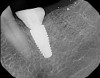

After a 6- to 8-week healing period, the custom healing abutment was removed to allow for a digital scan of the area as an alternative to conventional impression-taking (Figure 15 and Figure 16). An intraoral scan body was used to capture the soft-tissue profile and implant positioning with an intraoral scanner (CEREC® Omnicam, Dentsply Sirona) (Figure 17). Final seating of the restoration was performed with radiographic confirmation (Figure 18). The implant crown demonstrated a natural emergence profile to replace the mandibular first molar with optimized tissue fill in the interproximal regions (Figure 19).

Fig 18. Radiograph of the final restoration after the customized emergence profile had been developed, replicating a natural emergence.